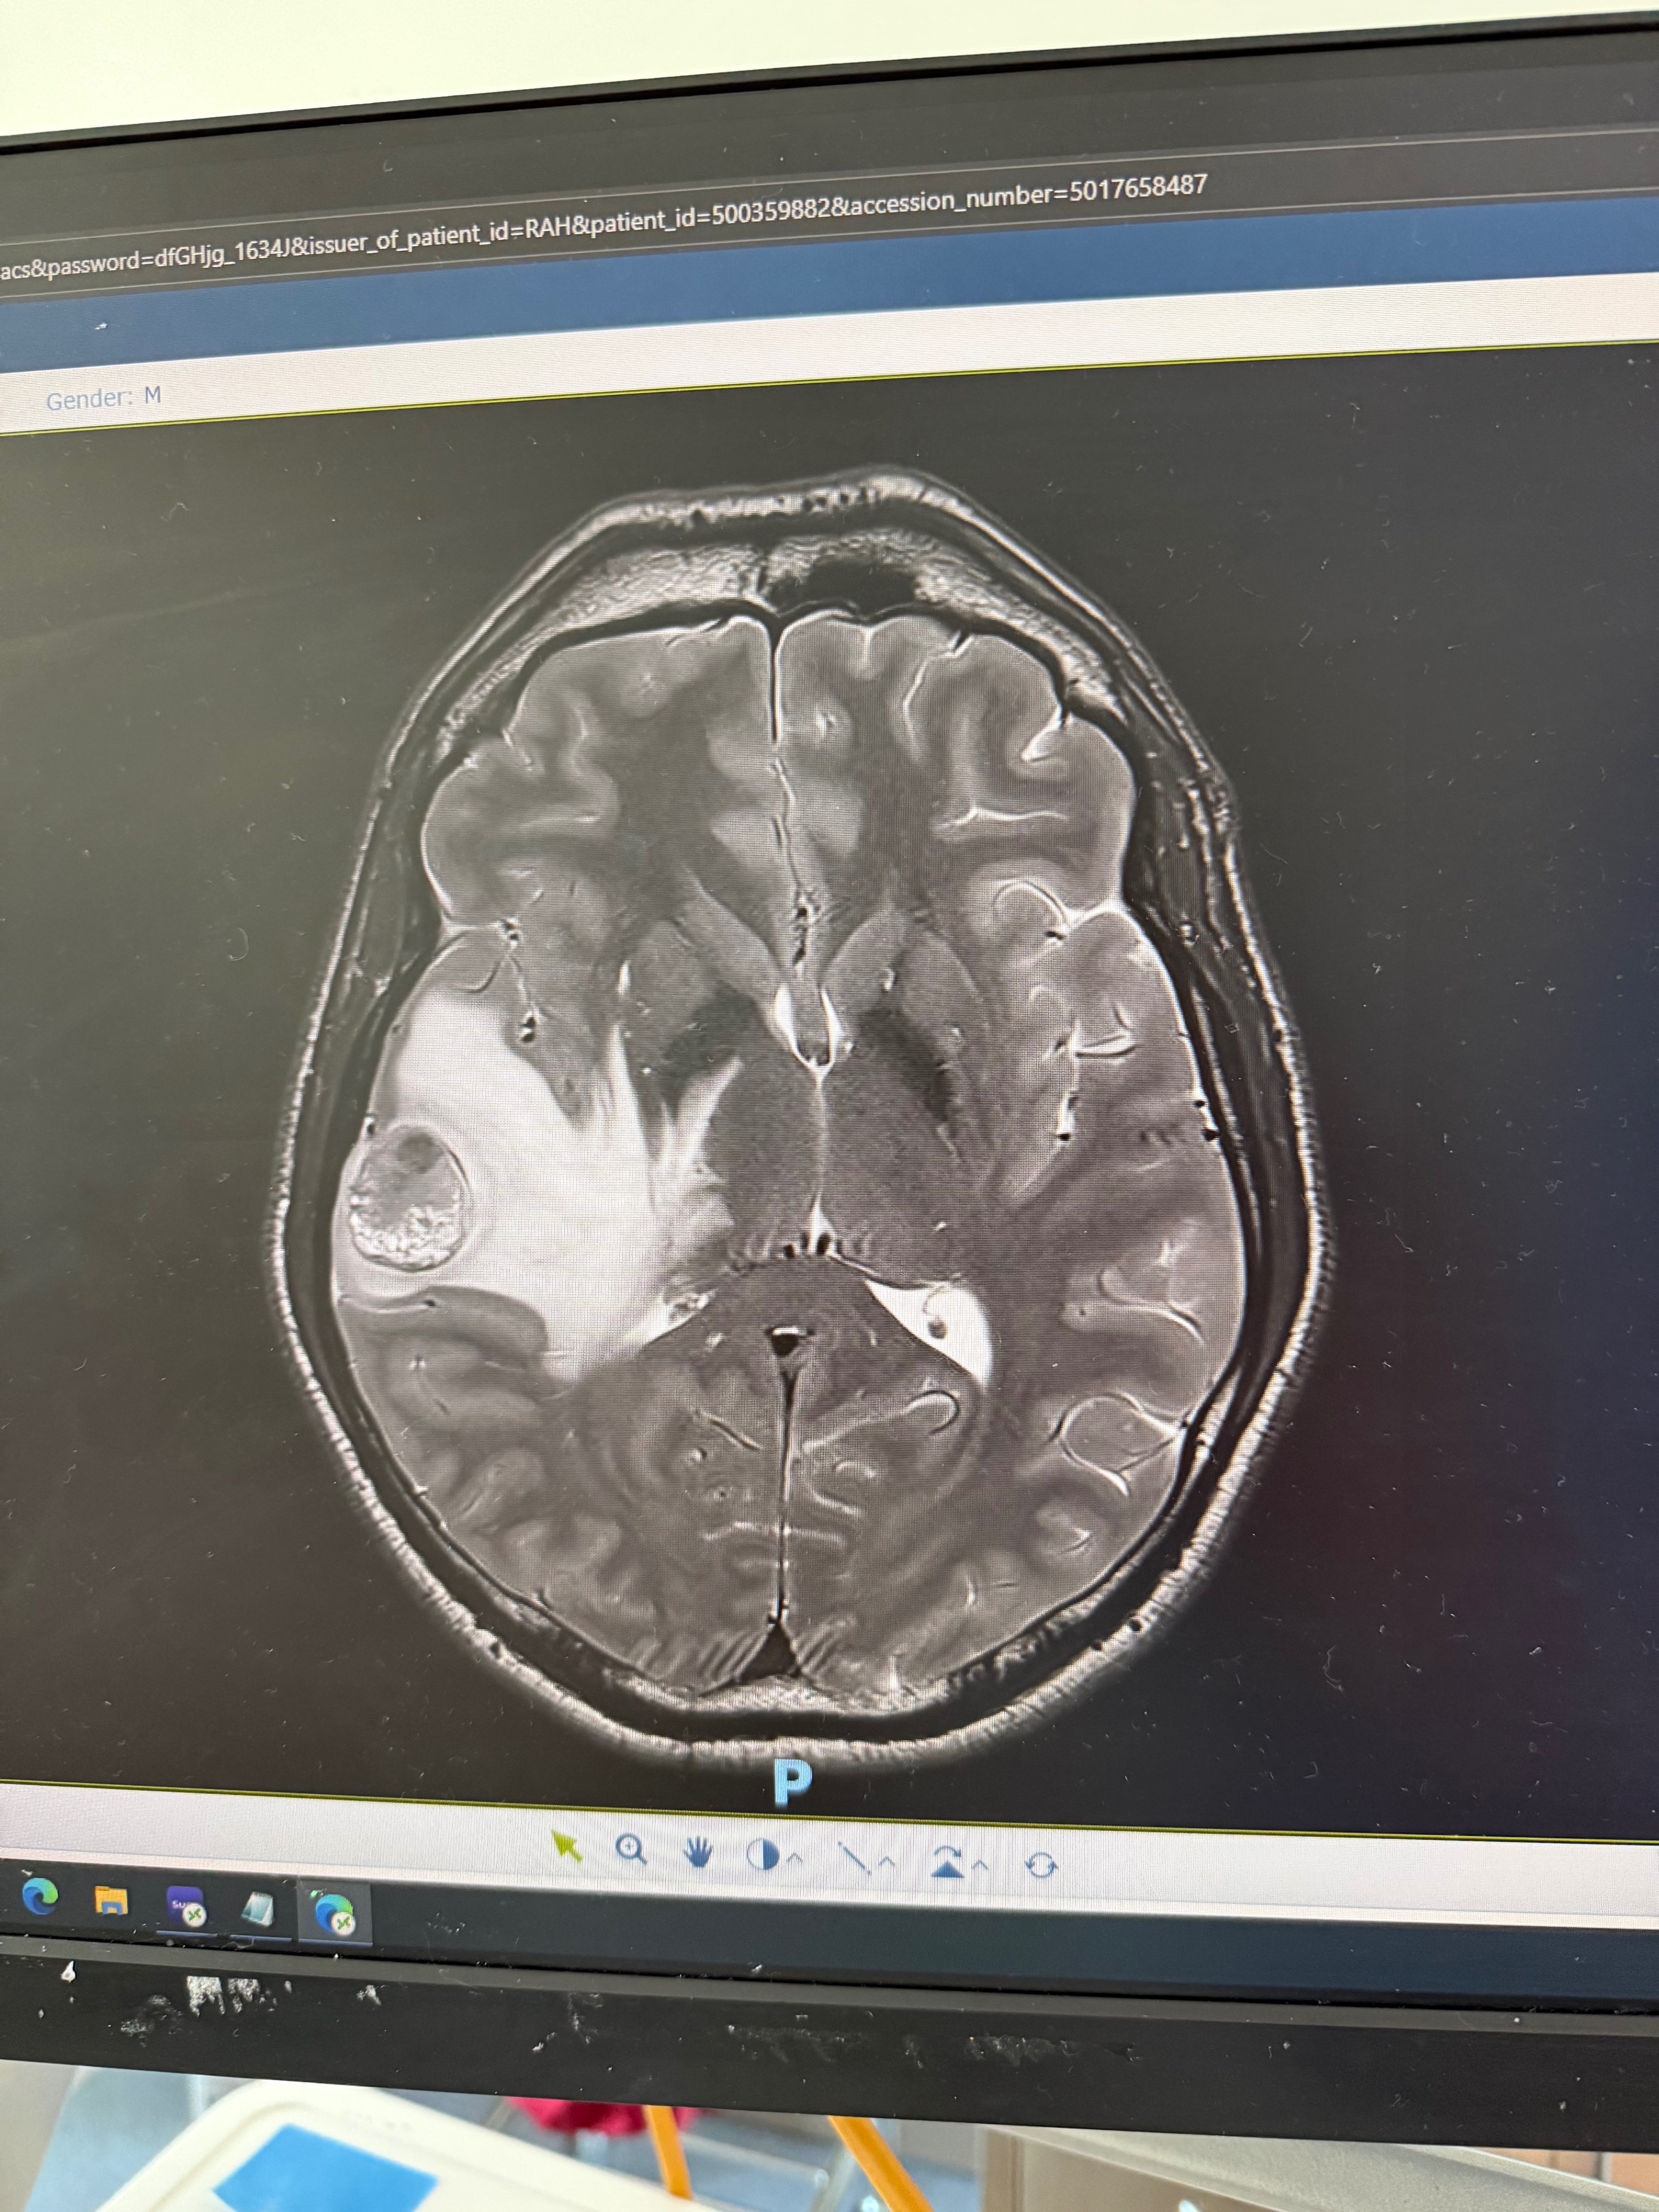

As some of you know, the end of 2025 wasn’t a positive one for our family. Just before Christmas we received the news that my brother Ross had a brain tumour that was causing huge amounts of swelling on his brain and needed to be removed immediately.

Ross started getting headaches in early December, but having had a sinus surgery at the end of November he assumed it was related to that. Quite quickly these headaches ramped up and were accompanied by vomiting episodes and by the 18th December he called an ambulance as he couldn’t feel his hands or feet. He was taken to the Royal Adelaide Hospital where they discovered the brain tumour and various other masses in his body. He underwent a craniotomy where the tumour was successfully removed and sent away for testing. He is recovering remarkably well post-op and we were able to have Christmas together as a family.

Devastatingly, we have been told that he has Stage 4 Melanoma with metastases to his brain, lymph nodes, lungs and pelvis. He is having a PET scan this week to determine where else the cancer has potentially spread. At this stage the treatment will most likely involve a combination of radiation, immunotherapy and chemotherapy with an unknown prognosis.